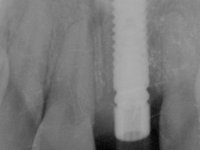

A paciente apresenta um desvio da linha média superior de 6 mm para a esquerda. Resultado da ausência do incisivo central superior esquerdo, os dentes adjacentes inclinaram mesialmente para esta zona, limitando o espaço disponível para a reabilitação prostodontica. Existe uma significativa desarmonia dentária negativa no arco maxilar como resultado da ausência do 21, ausência do primeiro pre-molar com um espaço residual, significativa redução coronária do segundo pre-molar direito, migração dos dentes posteriores para os espaços não preenchidos e uma mesialização molar superior esquerda e direita com uma relação molar em Classe II. Ambos os caninos esquerdo e direito mostram uma relação Classe II na posição de inter-cuspidação máxima. A paciente apresenta uma linha de sorriso média, um biótipo gengival médio grosso, apresenta uma correcta higiene oral sem doença periodontal. Não apresenta hábitos para –funcionais. O exame radiográfico mostra uma significativa inclinação dos eixos dos dentes 11 e 22 com espaço entre a porção apical das raízes. A análise cefalométrica foi feita com o intuito de explorar a hipótese de conseguir arranjar espaço para a colocação de um implante e de uma coroa no local do dente 21. Finalmente a morfologia do osso residual presente na região anterior da maxila foi avaliado com uma TAC, revelando uma perda das dimensões da parede óssea vestibular.

3) Colocação de um implante no espaço criado na zona do 21 associada a uma regeneração óssea guiada da zona,

4) Reabilitar prostodonticamente o implante com um coto de oxido de zirconio e uma coroa de cerâmica vítrea prensada de dissilicato de lítio no sentido de obter o resultado estético pretendido.